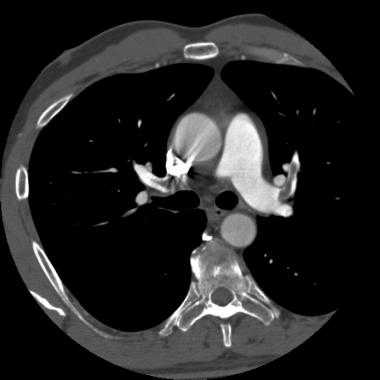

КТ-признаки ТЭЛА. На КТ-ангиограмме, выполненной 53-летнему пациенту, визуализируется внутрипросветный дефект наполнения; имеет место окклюзия артерии переднего базального сегмента нижней доли правого легкого. Определяются также признаки инфаркта правого легкого в виде участка консолидации треугольной формы, широким основанием обращенного к плевре (бугорок Хэмптона).

В большинстве случаев, когда на КТ обнаруживаются положительные признаки ТЭЛА, эмболы являются множественными, а внутрипросветные дефекты наполнения сосудов (дефекты контрастирования) визуализируются в более крупных центральных артериях, а также в сегментарных и субсегментарных сосудах. Чаще всего эмболы обнаруживаются с обеих сторон и локализуются в нижнедолевых артериях. Явный дефект наполнения в единственном сегментарном или (особенно) субсегментарном сосуде бывает сложно распознать. Необходимо учитывать, что за дефект наполнения субсегментарной артерии могут приниматься артефакты, связанные с эффектом частичного объема.